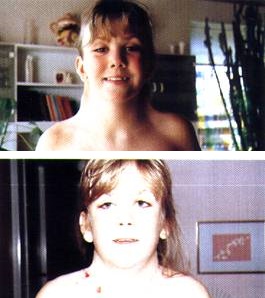

6- Síndrome de Cri Du chat o 5 p

El síndrome de Cri du Chat, conocido también por el síndrome del maullido de gato, es uno de los desórdenes cromosómicos producido por una deleción al final del brazo corto del cromosoma 5.

Afecta a uno de cada 20.000-50.000 recién nacidos y se caracteriza por el llanto que suelen tener estos bebés, asemejándose al maullido de un gato, de ahí su nombre.

Normalmente la mayoría de estos casos no son heredados, sino que es durante la formación de las células reproductivas cuando se pierde material genético.